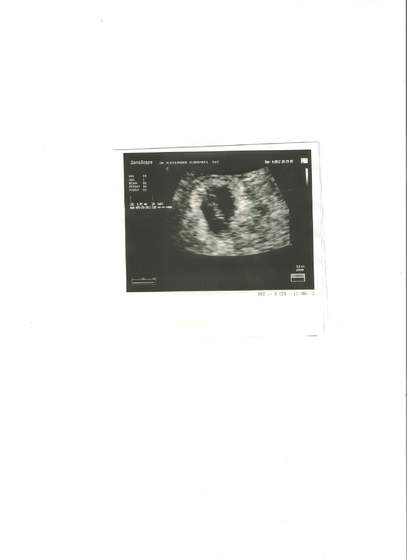

Widziałąm swoje 6 mm szczęscie, widziałam serduszko, mam kartę ciąży , nie mogę w to w uwierzyć lidka.jpg

Mam brać luteinę, stwierdził że kłucia mogą być a bołe jak na @ nie bardzo wieć lepiej dmuchać na zimne, następna wizyta za 3 tyg:-D:-D:-D

Ciaża o dwa dni młodsza niż ja obstawiałam, wczoraj był 6 t 2 dni, cieszę sie ze nastepna wizyta za 3 tyg, mam nadzieję ze szybko zleci